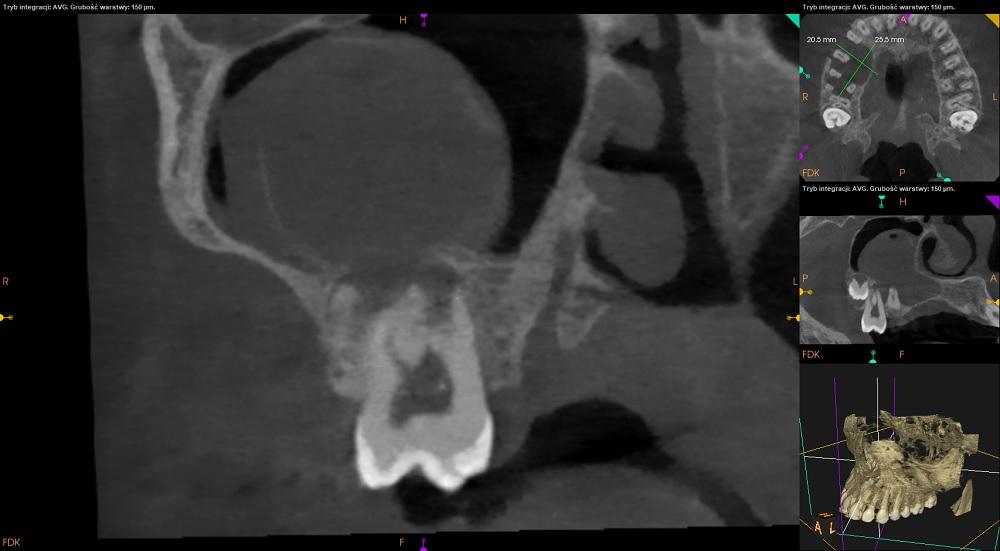

Tomografia szczęka.

Zatoka szczękowa prawa patologicznie zmieniona. Zatoka niepowietrzna w około 80% swojej objetości.

Regularny kopułowaty kształt zacienienia oraz obecność rąbka kostnego na górnej powierzchni zacienienia sugerują zębopochodne pochodzenie zmiany.

Ubytek w ścianie przedniej zatoki szczękowej prawej.